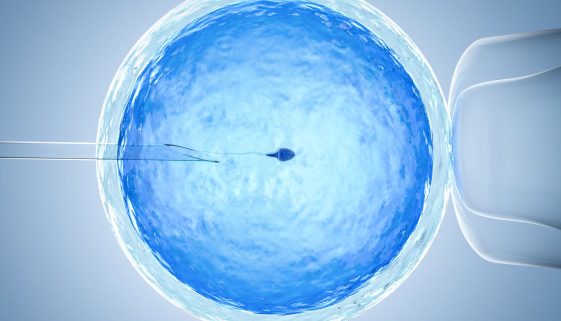

زيادة فرص الإنجاب للنساء: نصائح وتعليمات تثقيفية

يمثل موضوع الخصوبة والإنجاب أهمية كبيرة للكثير من النساء حول العالم. يصنف الكثير هذا الموضوع كأحد الأولويات في حياتهم. ومع تقدم العلوم وزيادة الوعي بالصحة الإنجابية، أصبح من الممكن تحسين فرص الإنجاب باتباع بعض النصائح والإرشادات البسيطة. في هذه المقالة، سنناقش بعض النصائح المهمة التي يمكن أن تزيد من فرص […]